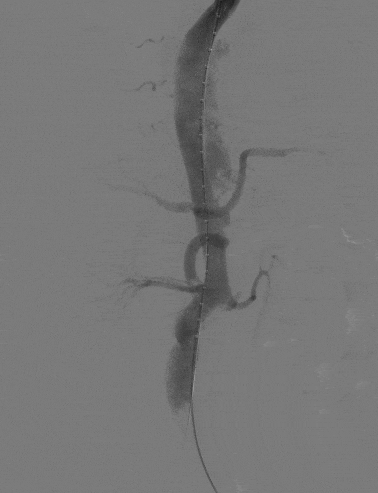

4、术后造影显示,主动脉夹层第一破口被有效隔绝,LSA血流通畅,真腔得到有效重塑,支架无移位或内漏现象发生,手术圆满成功。

动脉长鞘怎么置入宁波市第二医院血管外科运用Castor®单分支支架结合长鞘建立导丝通路的方法治疗Stanford B型胸主动脉夹层一例_https://www.jmylbn.com_新闻资讯_第12张

术后造影

动脉长鞘怎么置入宁波市第二医院血管外科运用Castor®单分支支架结合长鞘建立导丝通路的方法治疗Stanford B型胸主动脉夹层一例_https://www.jmylbn.com_新闻资讯_第13张

术后造影(胸腹主动脉)